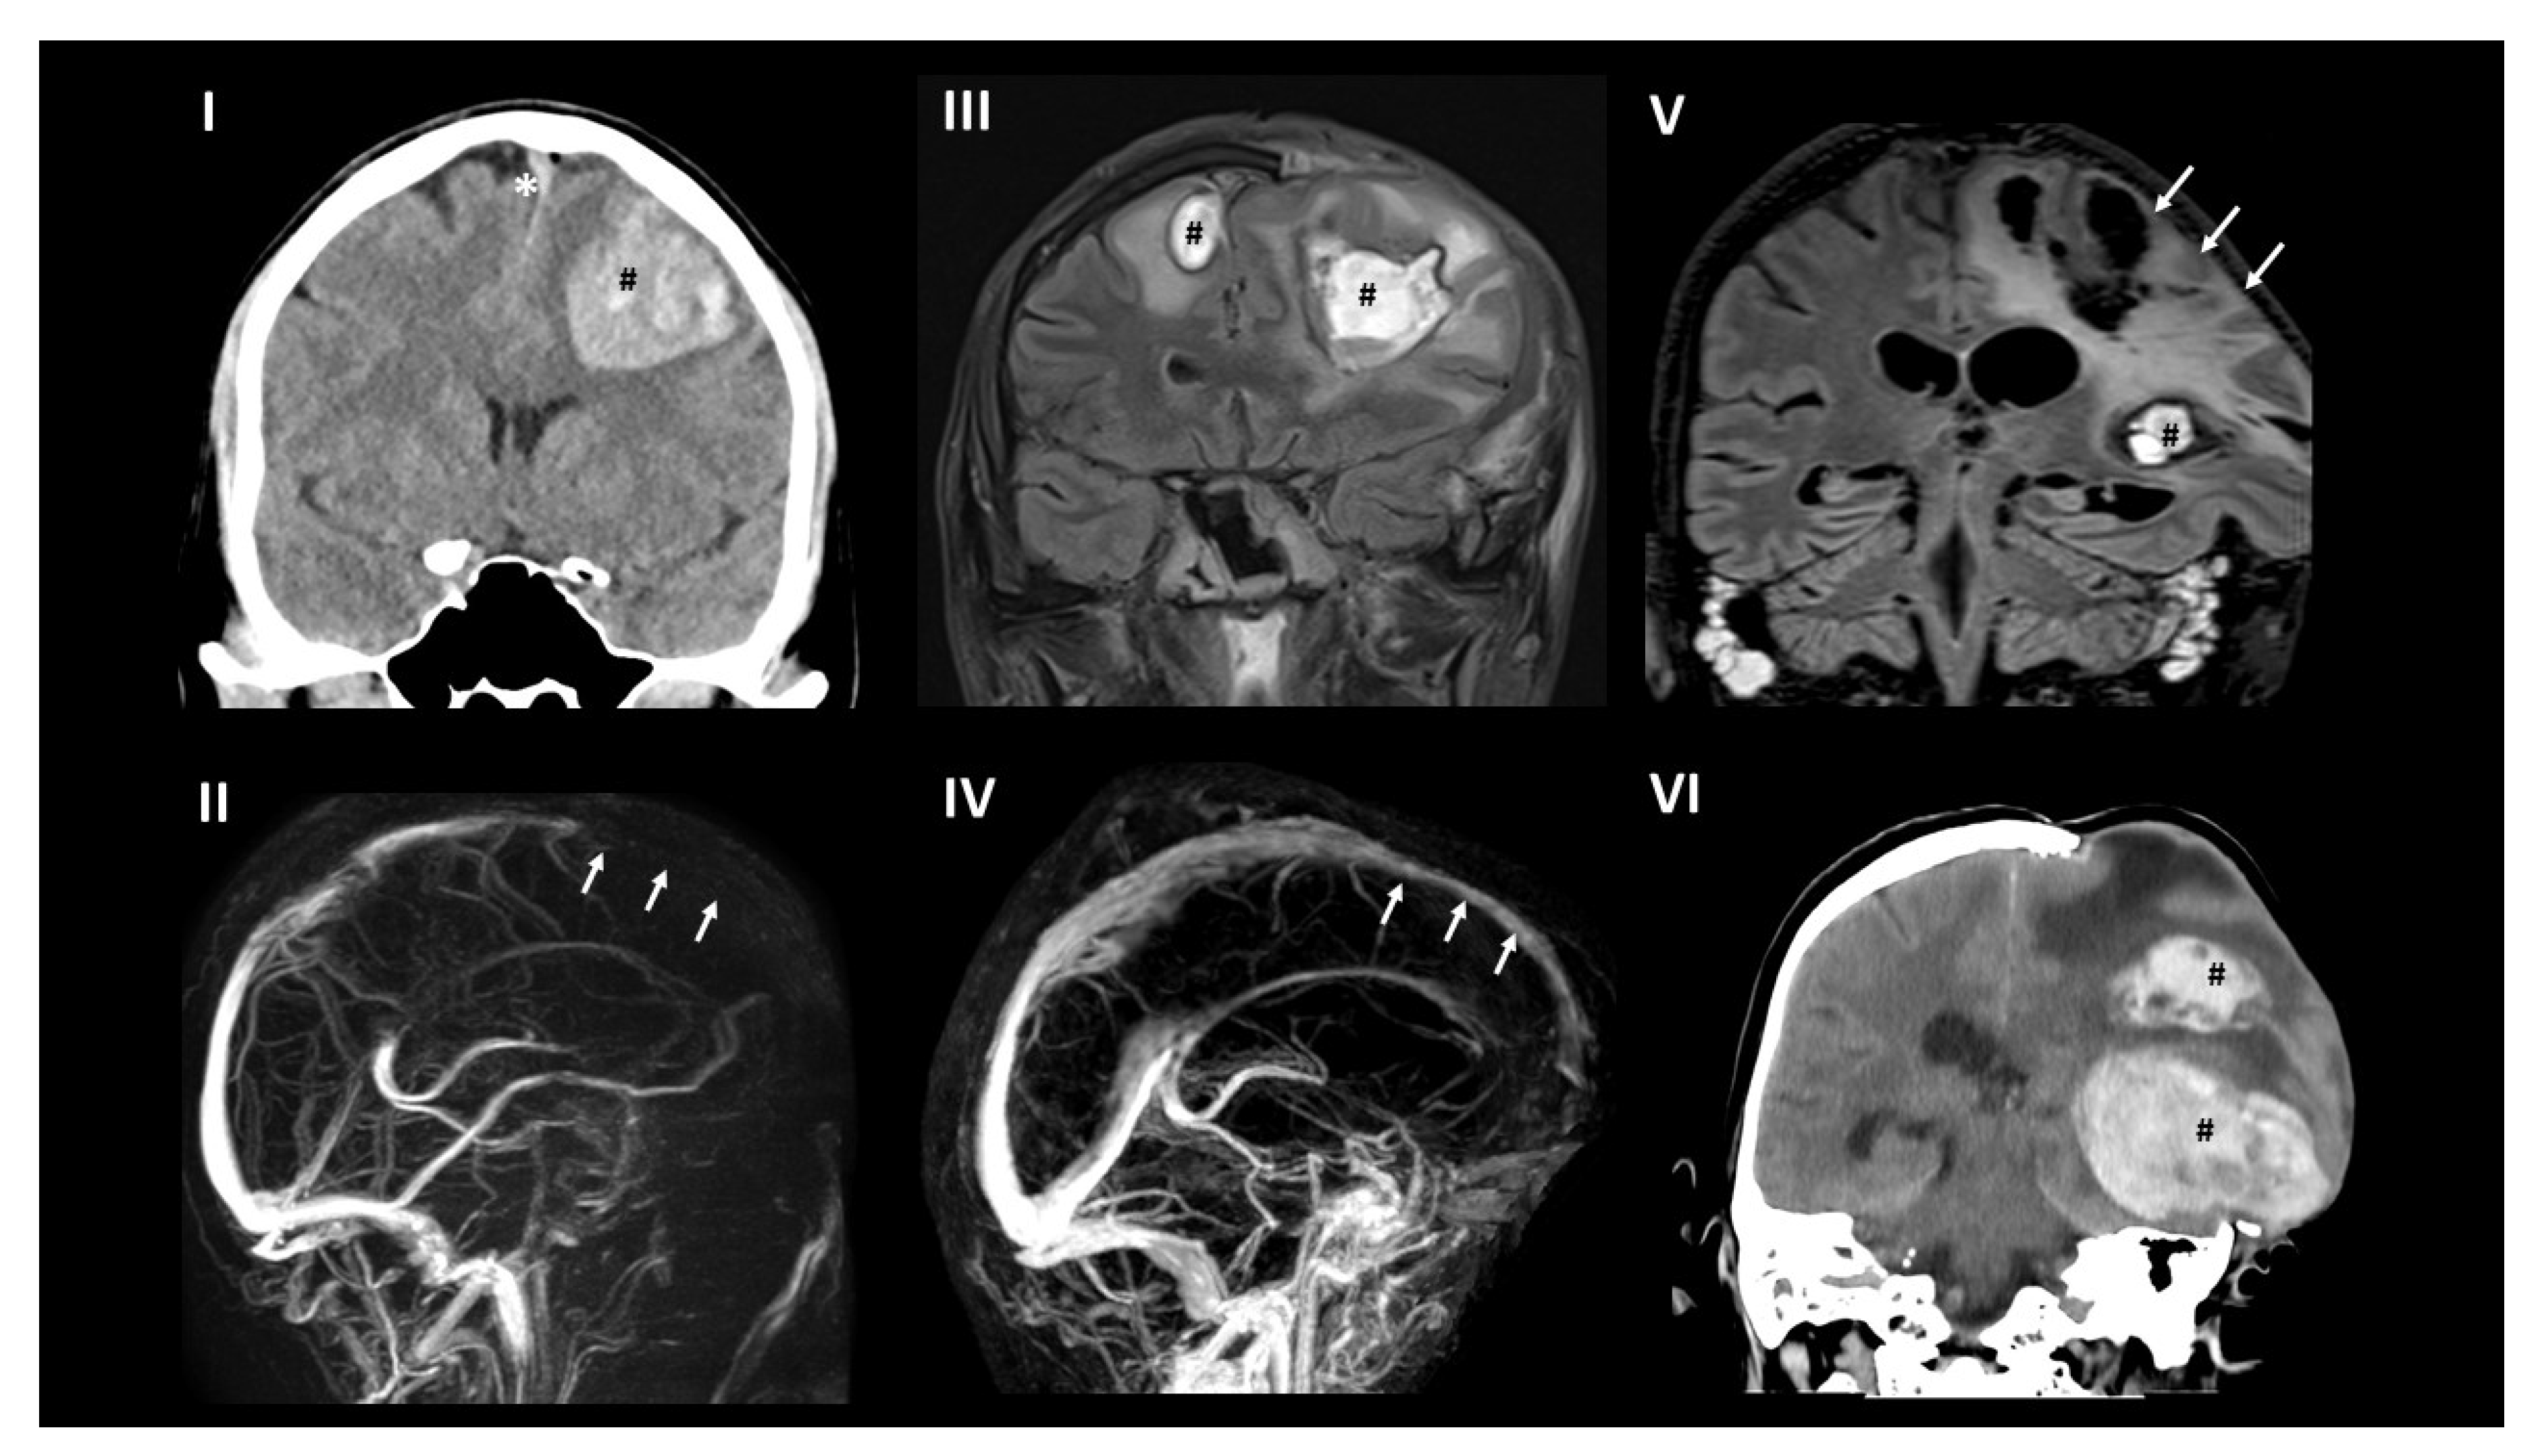

2. Case Report

3. Brain Imaging